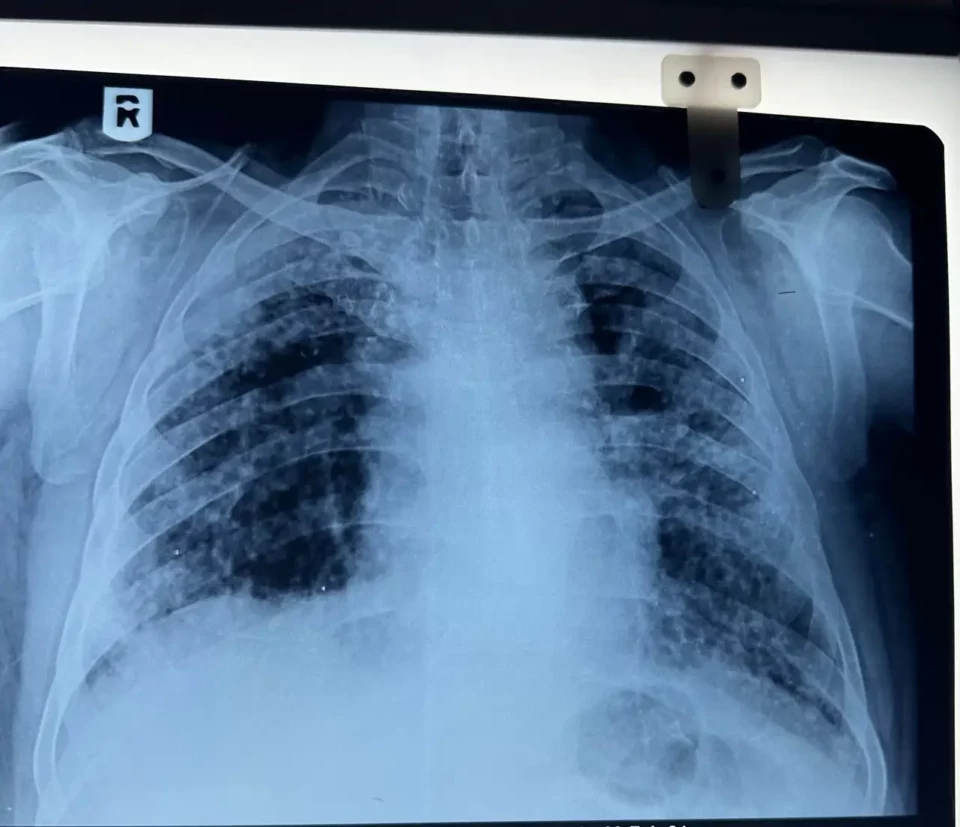

La silicosis es una dolencia incurable provocada por la inhalación prolongada de partículas de sílice cristalina, una sustancia que se libera al cortar o pulir estos materiales compuestos. Su presencia en el aire es imperceptible, pero su efecto en los pulmones es devastador: fibrosis pulmonar, deterioro respiratorio progresivo y, en muchos casos, una muerte prematura.

Así, desde 2018, además, se han documentado 46 partes de cáncer de pulmón directamente relacionados con la exposición a sílice, 19 de ellos en el último año. La silicosis, lejos de ser la única consecuencia de este polvo letal, aparece también asociada a enfermedades autoinmunes, como la artritis reumatoide, y a afecciones cardíacas. En el 60 % de los casos, se diagnostican patologías inmunomediadas junto con la silicosis. Esta combinación complica el diagnóstico, retrasa los tratamientos y agrava el pronóstico de los afectados.